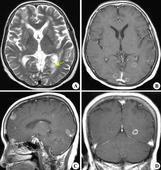

室管膜瘤(ependymoma)發生于腦室的室管膜細胞,占兒童中樞神經系統原發性腫瘤5%~10%。好發于后顱窩,約60%。5歲以下兒童多見。瘤體多位于腦室內,少數在腦室旁組織內,呈緩慢、浸潤性生長。瘤細胞亦可脫落于蛛網膜下腔產生播散性種植。